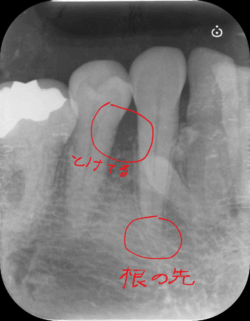

エンドぺリオ病変 〜歯周病なのに神経の治療が必要〜

基本的にエンドぺリオ病変の場合、根管治療を最初におこなう必要があります。 根管治療をおこなわず歯周病治療を先におこなってしまうと、原因の根本解決にならないだけではなく、状態をさらに悪化させてしまう場合があります。 だから最初の診断がとても重要になってきます。 根管治療が終了して3ヶ月後くらいから、歯周病治療を開始するのが良いとされています。